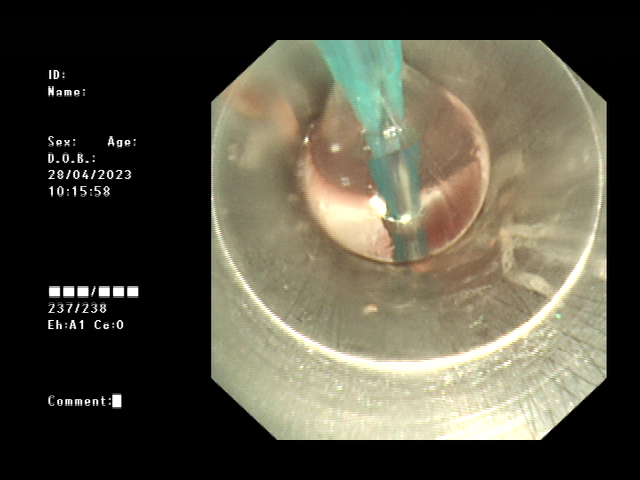

经过术前的充分准备,患者在全麻下,用可弯曲支气管镜引导插入法插入硬镜,通过高频电刀放射状切开狭窄环,再予气道球囊扩张器扩张气道置入硅酮支架,并置入喉罩复苏,最后成功为患者实施硬质支气管镜技术。术后,患者气道通畅,无呼吸困难、气促等症状出现,对比术前生活质量得到明显改善。

高频电刀切开狭窄环